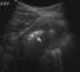

Pancreatic fat necrosis

Panniculitis is a group of diseases whose hallmark is inflammation of subcutaneous adipose tissue (the fatty layer under the skin – panniculus adiposus). Symptoms include tender skin nodules, and systemic signs such as weight loss and fatigue. [Source: Wikipedia ]